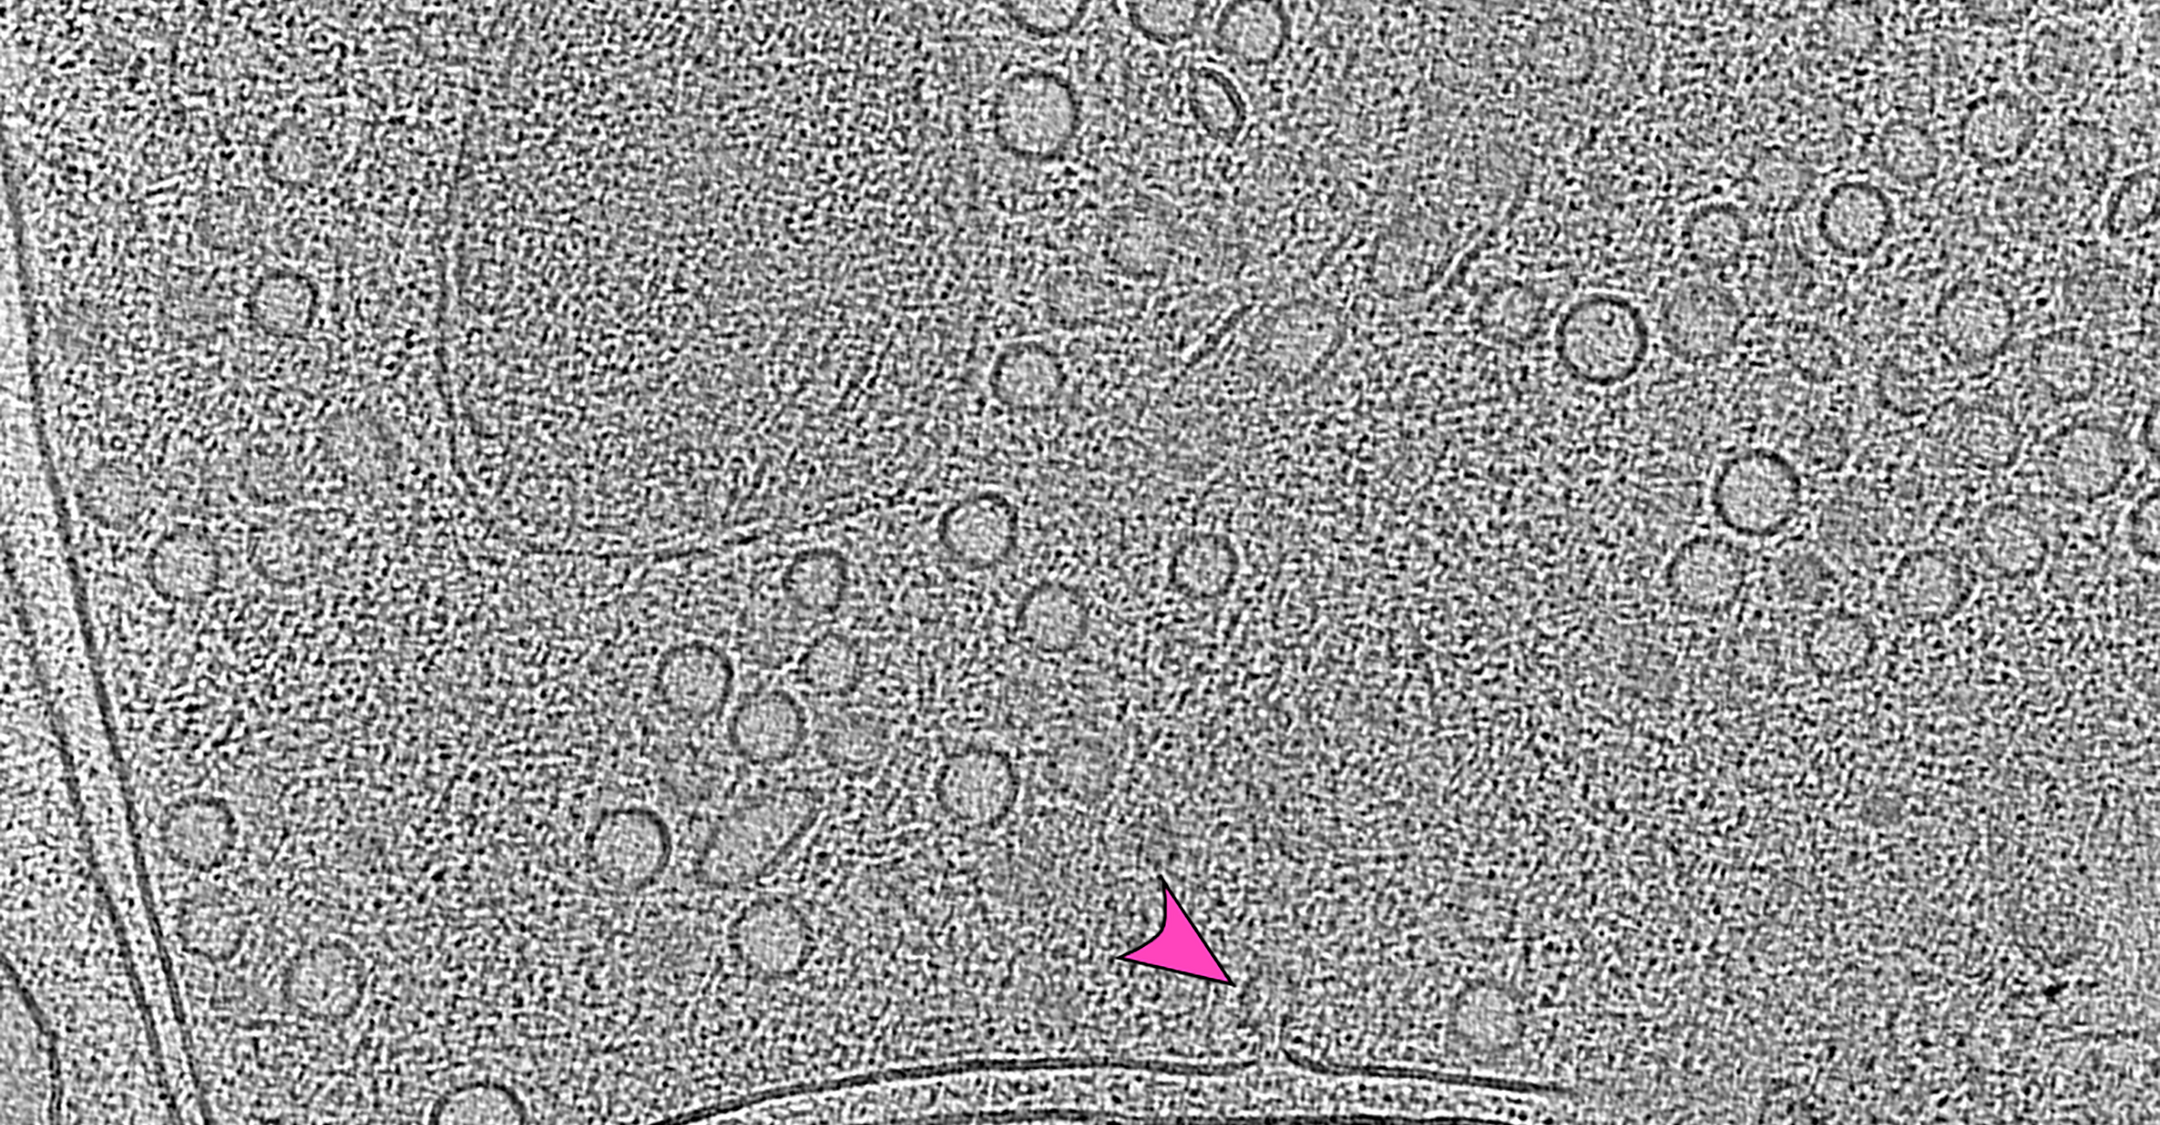

Observing synapses in action

A team of Berlin-based researchers led by Jana Kroll and Christian Rosenmund has captured the fleeting moment a nerve cell releases its neurotransmitters into the synaptic cleft. Their microscopic images and description of the process are published in “Nature Communications.”